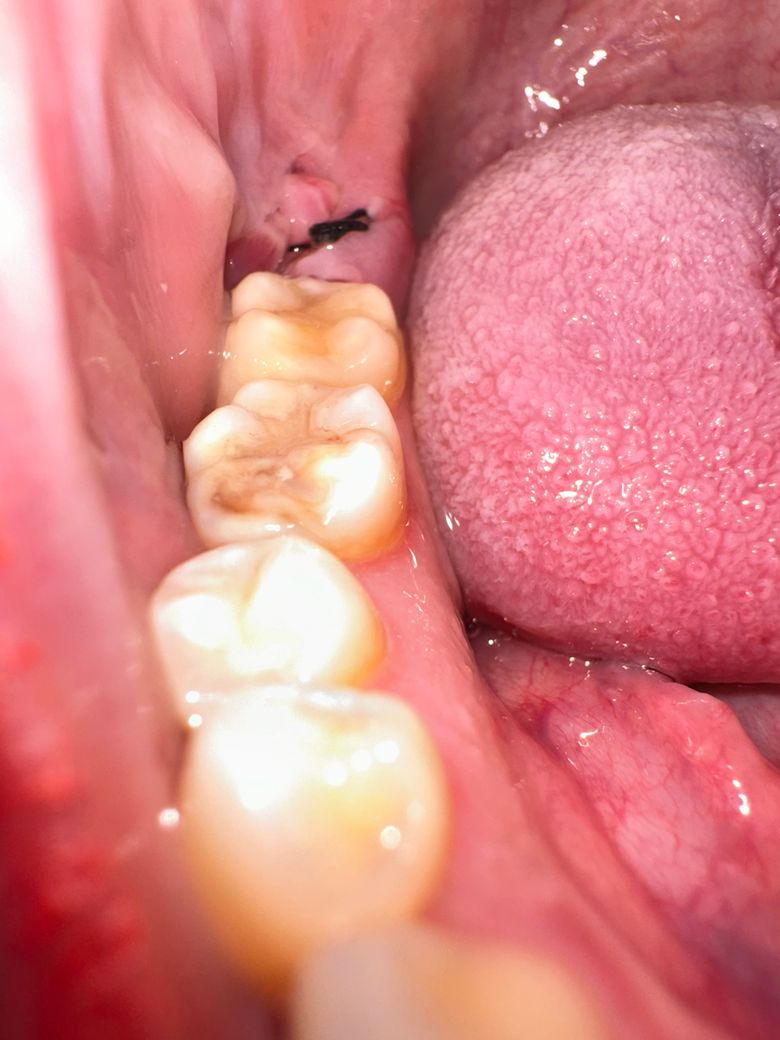

매복사랑니 발치 후 잇몸이 찢어진걸까요?

매복사랑니 발치하고 5일이 지났습니다

2일째 소독했을때 잘 아물고 있다고 했는데

4일째부터 이물감이 있어 확인하니

2일째와 생긴게 다르더라구여ㅜ

제가 관리를 제대로 못해서 잇몸이 찢어진걸까요?

혹시 잘 아물고 있는게 아닌지.. 문제가 있는지 확인 부탁드려요ㅠㅜ

• 1번 째 사진

정상적으로 아물고 있는 중으로 보입니다. 붓기가 가라앉으면 사랑니 뽑은 자리에 구멍이 생기는 경우가 대부분이지만 시간이 지나면 점점 좋아집니다.

사진상으로 보면 사랑니 발치를 하고나서 잇몸이 잘 아물고 잇는거 같습니다 크게 걱정하지 않으셔도 될것같습니다.

사진 상 판단이 한정적이기는 하나, 잘 치유되고 있는 양상으로 보입니다. 혹여나 궁금하다고 해당 부분을 건드려보시면 안됩니다.

특별히 잇몸 치유에 문제가 있는 상태는 아닙니다 발치 후 주의사항 잘 지켜주시고 너무 입 크게 벌리지 마세요